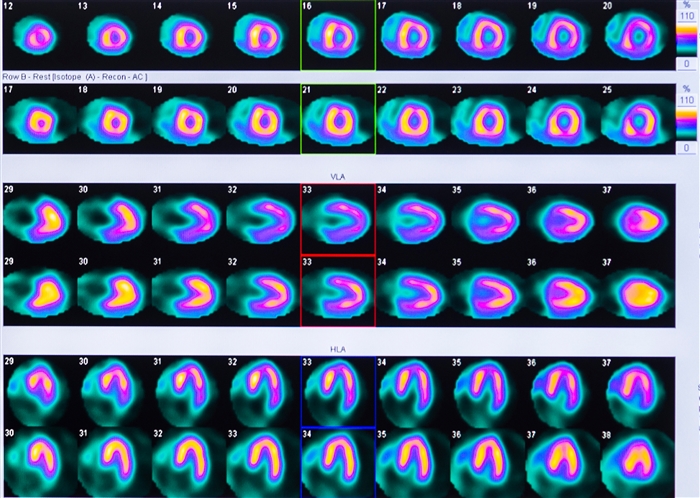

心筋シンチ

心筋シンチグラフィ、心筋スペクト

とも呼ばれます。

心筋シンチでわかること

心臓は全身に血液を送るポンプです。

このポンプの役割をするのは

心臓の筋肉です。

心筋シンチではこの筋肉に流れる

血液の流れを画像化します。

主に狭心症・心筋梗塞の診断や、

心筋梗塞でできた傷の範囲がわかります。

心臓の動きの評価もできます。

↓実際の心筋シンチの画像。 心臓の左心室の筋肉の血のめぐりの悪いところを見つけます。

↓心筋シンチでは、心臓の左心室の動きを計測することもできます。